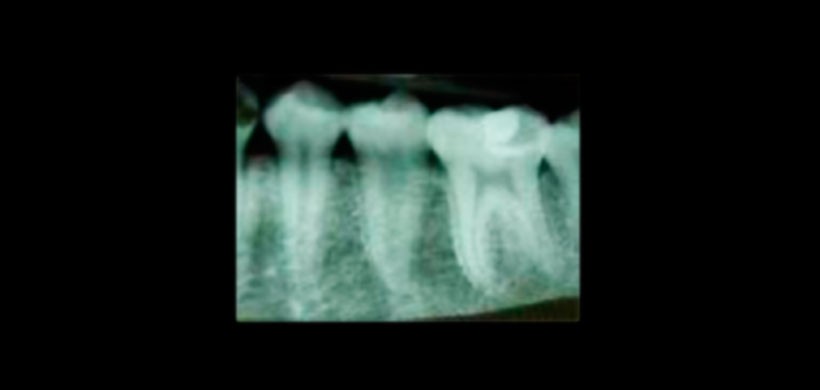

Figura 4: Radiografía final pos tratamiento de coducto.